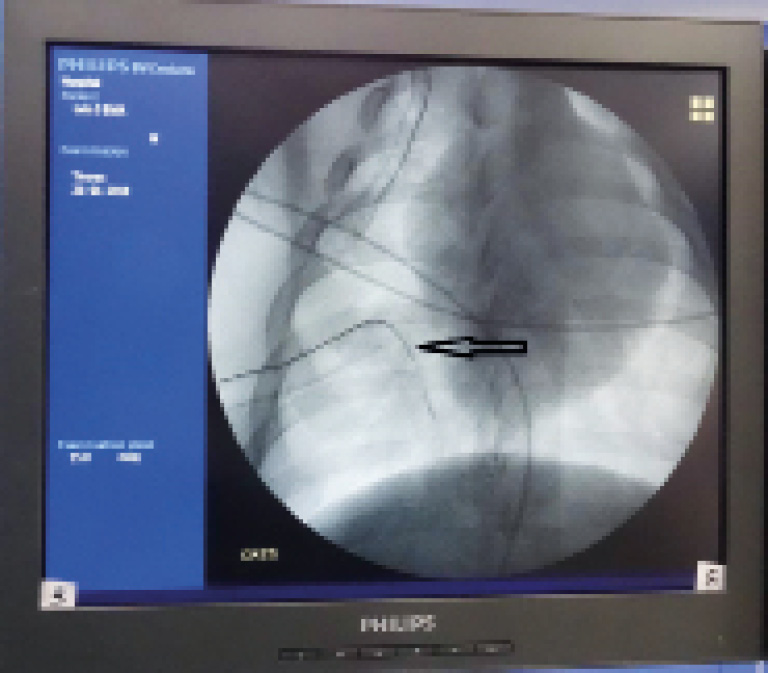

После 10-минутной экспозиции выполнялся прокол-разрез размером до 1,5 см в IV межреберье по среднеключичной линии, затем с использованием дренажного катетера (исполнение 1) вращательными движениями выполнялся прокол грудной стенки и париетальной плевры (рис. 4).

Рис. 4. Дренажный катетер (исп. 1) проведен вглубь плевральной полости на 4–5 см

Дренажный катетер проводился вглубь плевральной полости на 4–5 см, стилет извлекался. Свободный конец дренажного катетера присоединялся к удлинительной трубке, осуществлялось дренирование плевральной полости по Бюлау. Декомпрессия плевральной полости оценивалась по поступлению воздуха в дренажную систему и данным рентгенограммы груди (рис. 5).

Рис. 5. Рентгенограмма груди. Напряженный пневмоторакс ликвидирован, дренажный катетер визуализируется в IV межреберье